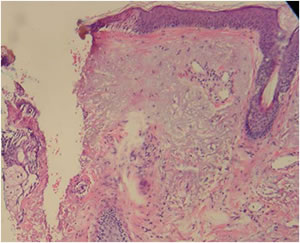

Histology

| Immediate post-treatment histology | Day four histology |